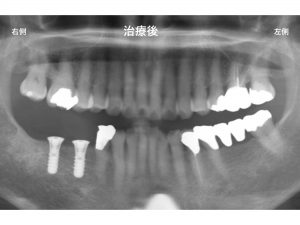

そして治療終了後です。

患者様は、今まで右側の奥歯で噛めなかったのが

噛めるようになり、食事も十分できるようになったため、大変喜ばれていました。